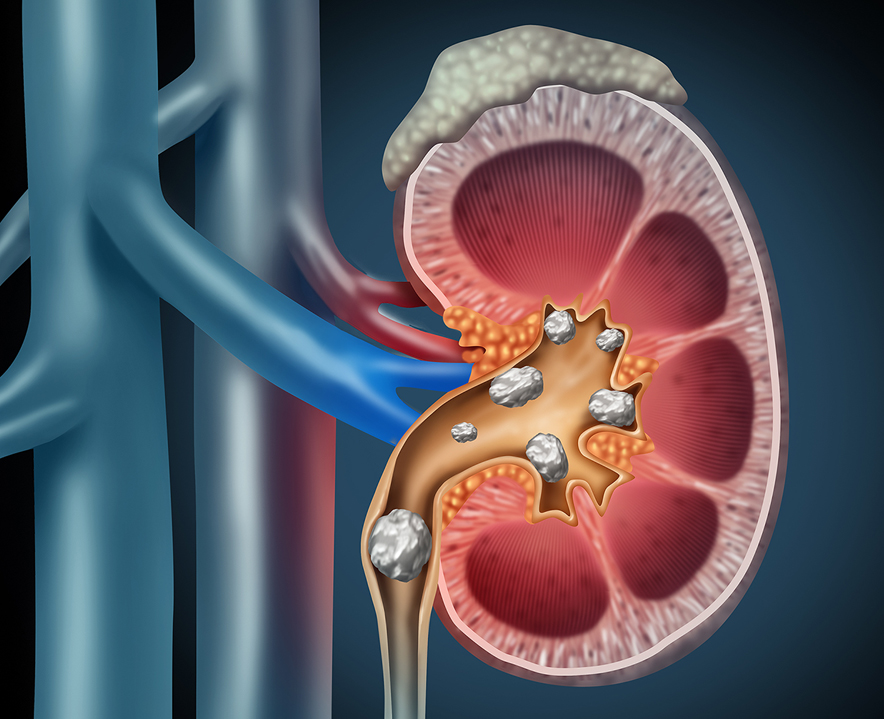

We are proud to provide specialized dialysis services such as hemoperfusion for paraquat poisoning, reflecting our commitment to managing complex and life-threatening conditions. Our expertise also extends to advanced kidney stone treatments using laser and minimally invasive endoscopic procedures including RIRS, URSL, and PCNL.

Kidney Stone Treatment (Laser & Endoscopic – RIRS, URSL, PCNL)

Minimally invasive and laser-assisted stone removal procedures.